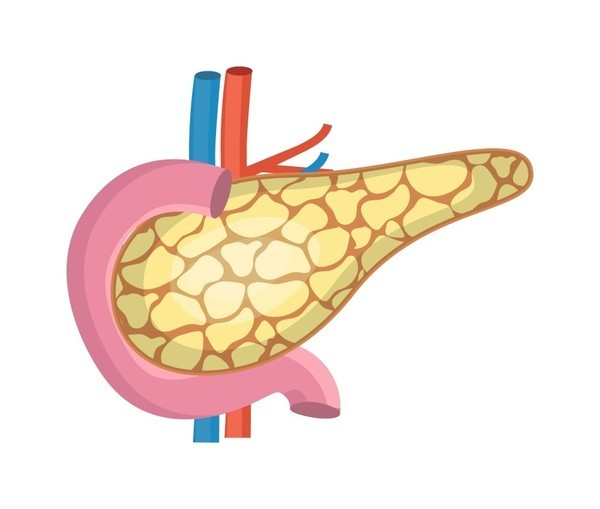

췌장은 해부학적으로 두부(머리 부분), 체부(몸통 부분), 미부(꼬리 부분)로 나눠집니다. 두부는 담관(담즙의 배출 통로)과 연결되어 있어 두부에 췌장암이 발생하면 담관이 막히면서 황달이 일어날수 있어요.

미부는 비장과 연결되어 있죠. 소장과 대장 일부에 혈액을 주는 상장간막 동맥은 대동맥으로부터 분지 되어 췌장과 인접해 주행하죠. 췌장에 일어나는 종양은 인슐린 등 호르몬을 분비하는 내분비 세포에서 출현하는 종양(5~10%)과 소화 효소의 분비와 맺어진 외분비 세포에서 소망하는 종양(90% 이상)으로 나눌 수 있죠.